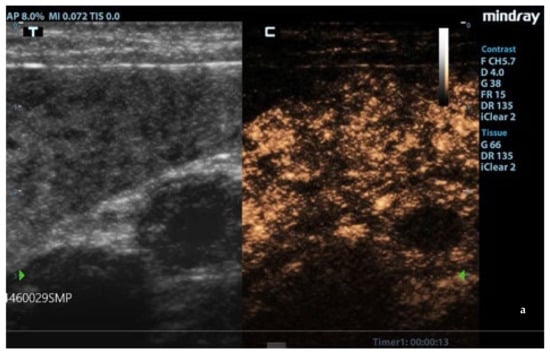

Figure 2.

Absence of signal at Color Power Doppler (CPD) in hypoechoic areas of the moth-eaten pattern of the spleen. F: probe’s frequencies; D: distance; G: gain; FR: frame rate; DR: dynamic range; AP: acoustic power; MI: mechanichal index; TIS: tissue imaging specific; M9: ultrasound system. Blue and green arrows: focal points.

3.2. B-Mode Ultrasonography

Splenic enlargement was found in 11/22 (50%) leishmaniotic patients. Overall, 7/11 (63.6%) had diffuse parenchyma abnormalities, which were always accompanied by an increased size (Figure 1). Parenchyma had a moth-eaten appearance in 4/7 and a marbled appearance in 3/7. In the remaining four, spleen was subjectively reported to be of a larger size than normal but with a normal echotexture. A positive correlation with the clinical stage of disease was detected for splenic enlargement (r = 0.634; p = 0.036) and diffuse parenchymal alterations (r = 0.655; p = 0.047). The correlation between ultrasonographic alteration and splenic quantitative PCR showed a low positive effect (r = 0.06; p = 0.779). Conversely, there was no correlation between spleen enlargement and echotexture with lymph node parasite load (r = 0.26; p = 0.573, r = −0.329; p = 0.4705, respectively) and IFAT title (r = 0.33, p = 0.1413, r = −0.38; p = 0.09, respectively). In none of the three dogs negative for L. infantum were splenic enlargement or abnormalities of echotexture detected. Upon CPD examination, flow signals were detected in both normal appearance and in moth-eaten and marbled spleens; under careful observation, CPD frames in moth-eaten spleens showed the absence of flow in the more visible hypoechoic foci (Figure 2).